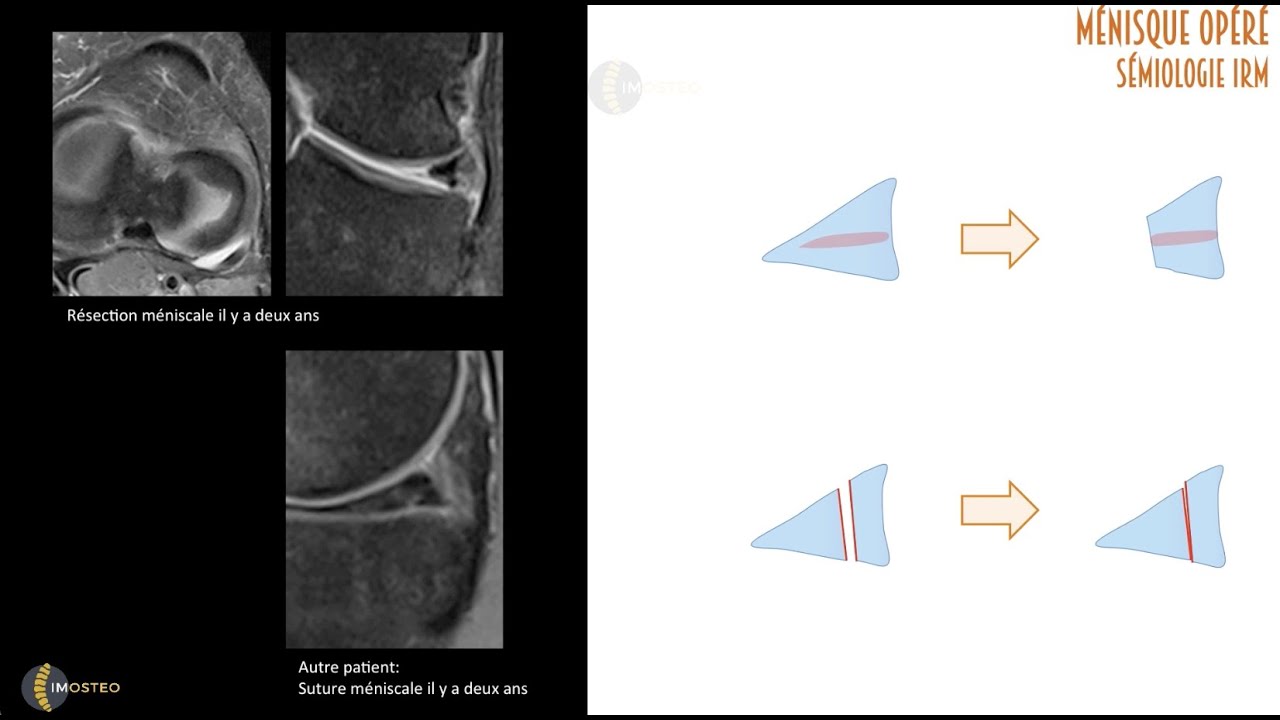

TUTORIEL IMOSTEO # 19 : Fissurations méniscales- Aspects post-opératoires